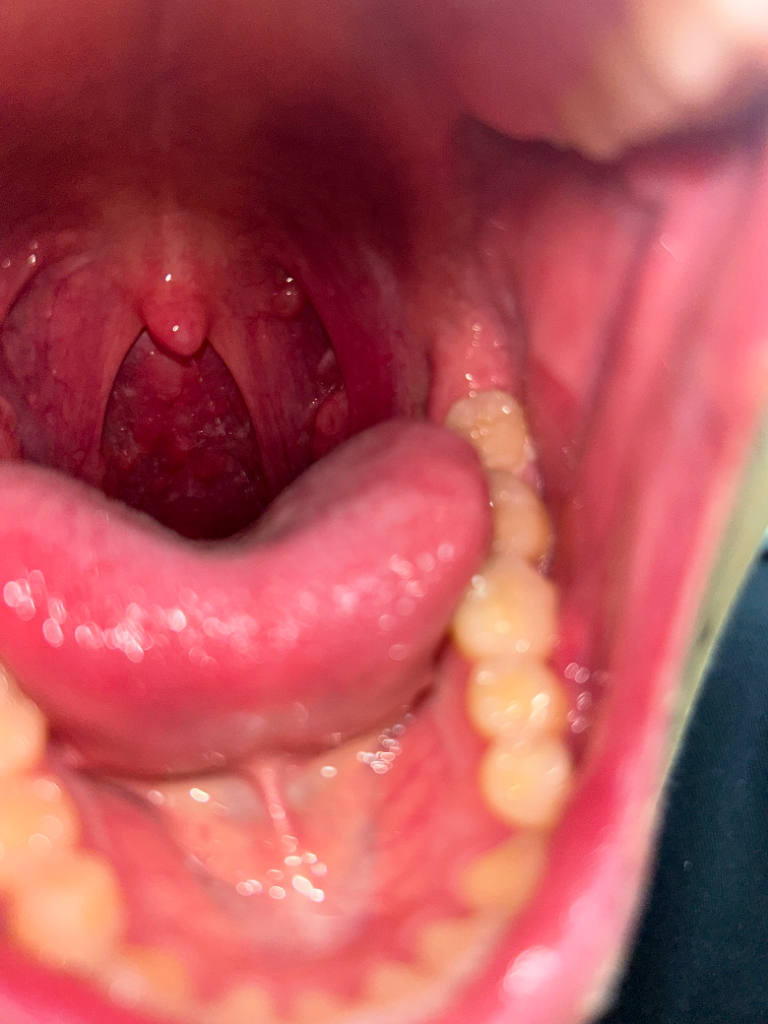

목에 이물감이 들고 침 삼키는게 불편해요

어느날부터 목에 이물감이 들고 침을 삼키는 게 불편해요 또 목구멍? 혀가 끝나는 지점하고 목구멍 쪽에 뭐가 오돌도톨한게 생겼어여 그리고 목에 자꾸 가래가 끼는듯한 느낌이 들어요 추가적으로 침에서 일반적인 침 냄세보다 조금 더 신 냄세가 나는 것 같아요 마지막으로 상관이 있을지는 모르겠지만 코로 숨쉬는게 많이 불편해요 ㅠㅠ

• 2번 째 사진

오돌토돌하다고 말씀하신 부분은 정상적인 림프조직인데, 인후통과 냄새가 사라지지 않아 고민이시라면 가까운 이비인후과를 방문해보시기를 권해드립니다.